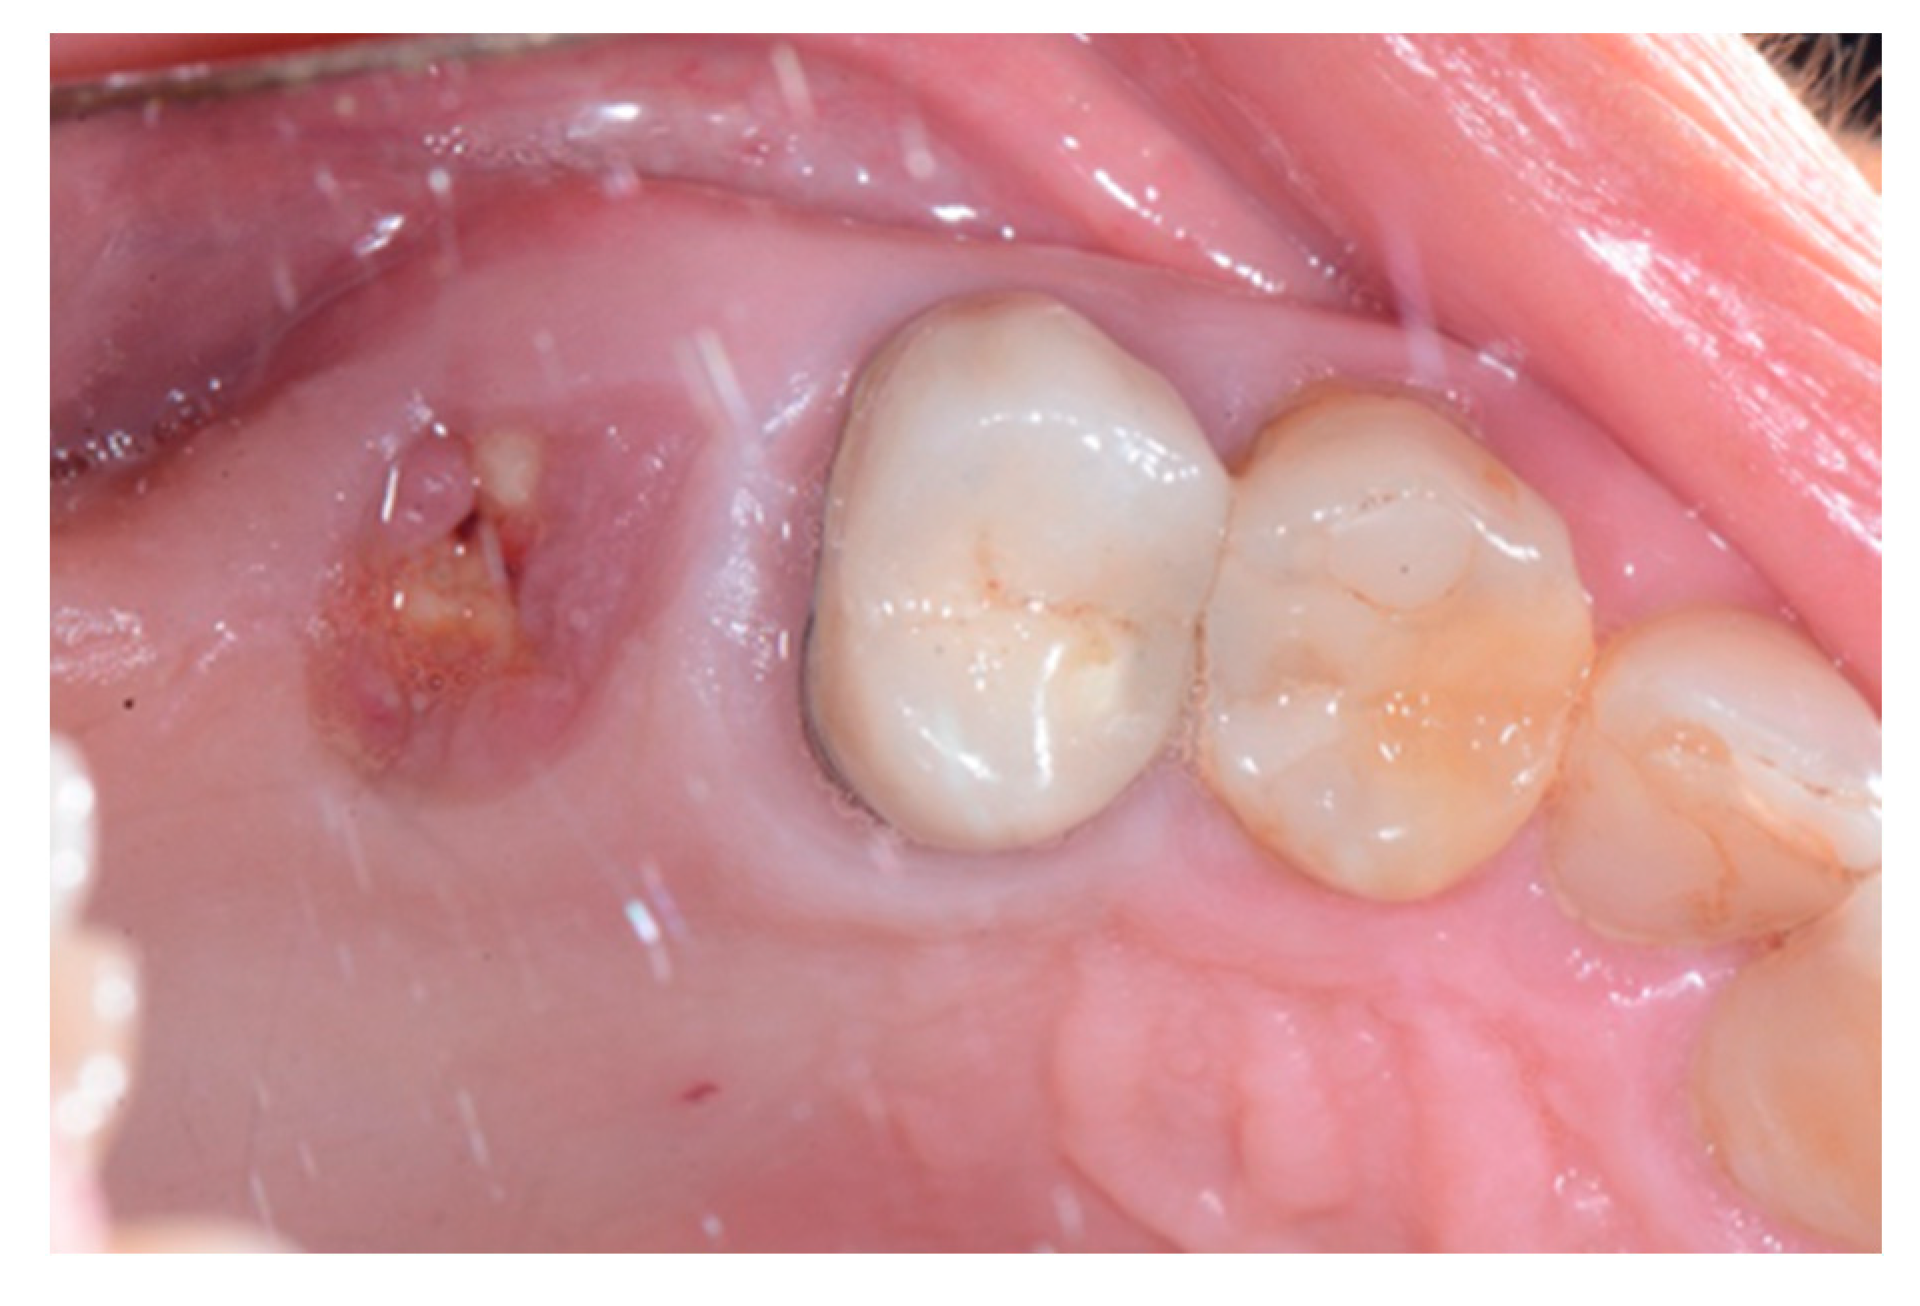

We used only surgical discarded material for the present study and the subject gave her informed consent before her participation. Seven days before the tooth extraction, the patient started prophylactic antibiotic therapy with amoxicillin/clavulanic acid (Augmentin, GlaxoSmithKline, Verona, Italy) and continued it for seven days after surgery 1 g/every 12 h, in addition to mouthwashes (chlorhexidine 0.2%) starting a week before surgery and continuing until healing occurred. Figure 2 shows the clinical situation after the crown removal. Once the extraction of tooth 26 (Figure 3) was carried out, the preservation of the alveolus was performed using a commercial enzymatically-deantigenated equine bone (Osteoxenon bone granules, Bioteck S.p.A, Vicenza, Italy) (Figure 4) and a commercial double layer of equine pericardium membrane (Heart pericardium membrane, Bioteck S.p.A., Vicenza, Italy) was used to cover and protect the site (Figure 5).

Figure 2.

Clinical situation after crown removal.